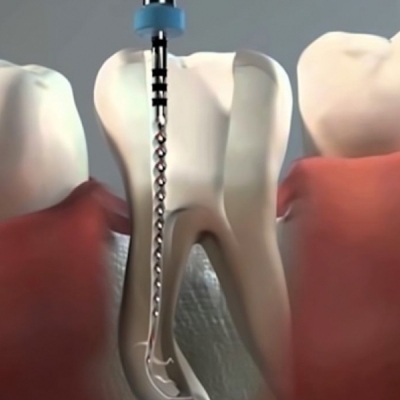

¿Cómo funciona un implante?

Reemplazamos la pieza dental original por una fabricada en Titanio biocompatible que se introduce en el hueso de la mandíbula, sobre ésta nueva raíz se fija una pieza de metal y cerámica (corona) resistente que se iguala en color y forma con el fin de brindar un aspecto lo más natural posible.

Se trata de un proceso sencillo e indoloro que le permitirá recuperar toda la funcionalidad de estética y de masticación.